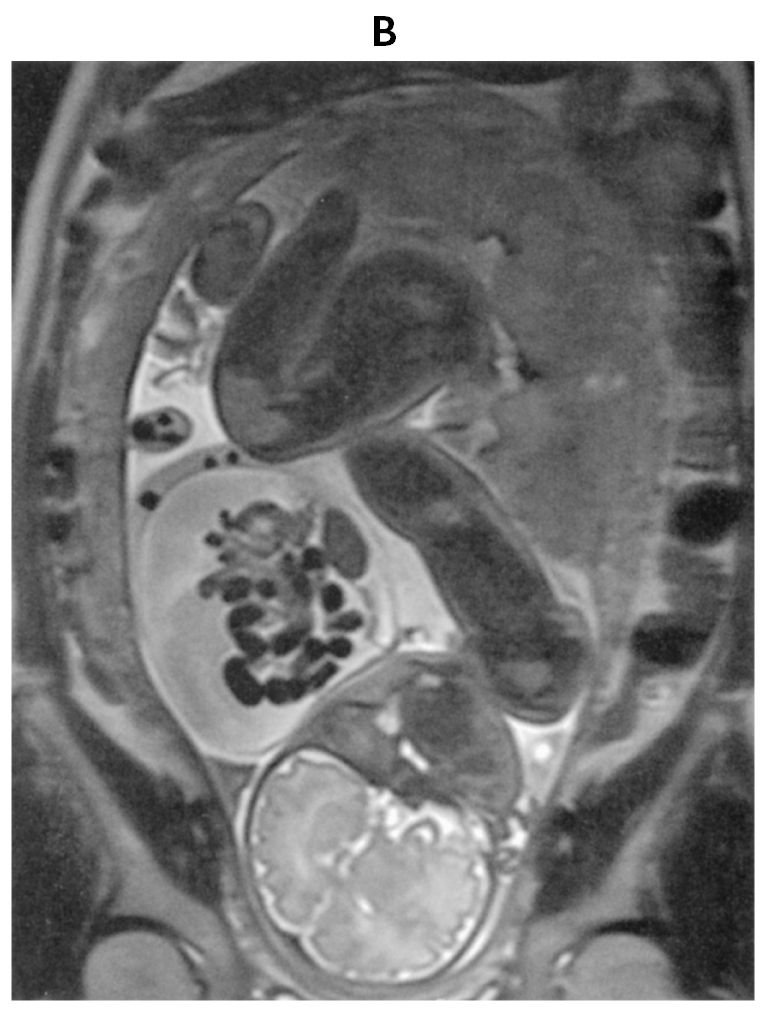

32歳の初妊婦(1妊0産)。妊娠20週時に胎児超音波検査で体外に臓器が脱出している所見を認めた。精査のために妊娠32週時に撮影した胎児単純MRIのT2強調矢状断像(A)(B)を下に示す。